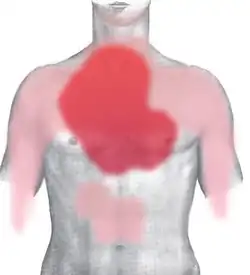

Rot: häufig und stark

Rosa: selten und schwächer

Eine schon in Ruhe spürbare AP gilt als „instabil“, d. h. es droht unmittelbar ein Herzinfarkt. Die Schmerzen werden oft als Brennen, „Sodbrennen“, Reißen oder krampfartiger Druck in der Herzgegend (Kardialgie) beschrieben, nicht links, sondern mittig hinter dem Brustbein. Es kann aber auch vorkommen, dass der Schmerz in Schultern und Oberarmen, Halsregion, in den Oberbauch und Rücken verortet wird. Dazu klagen die Betroffenen über Atemnot, kalten Schweißausbruch, und Todesangst.